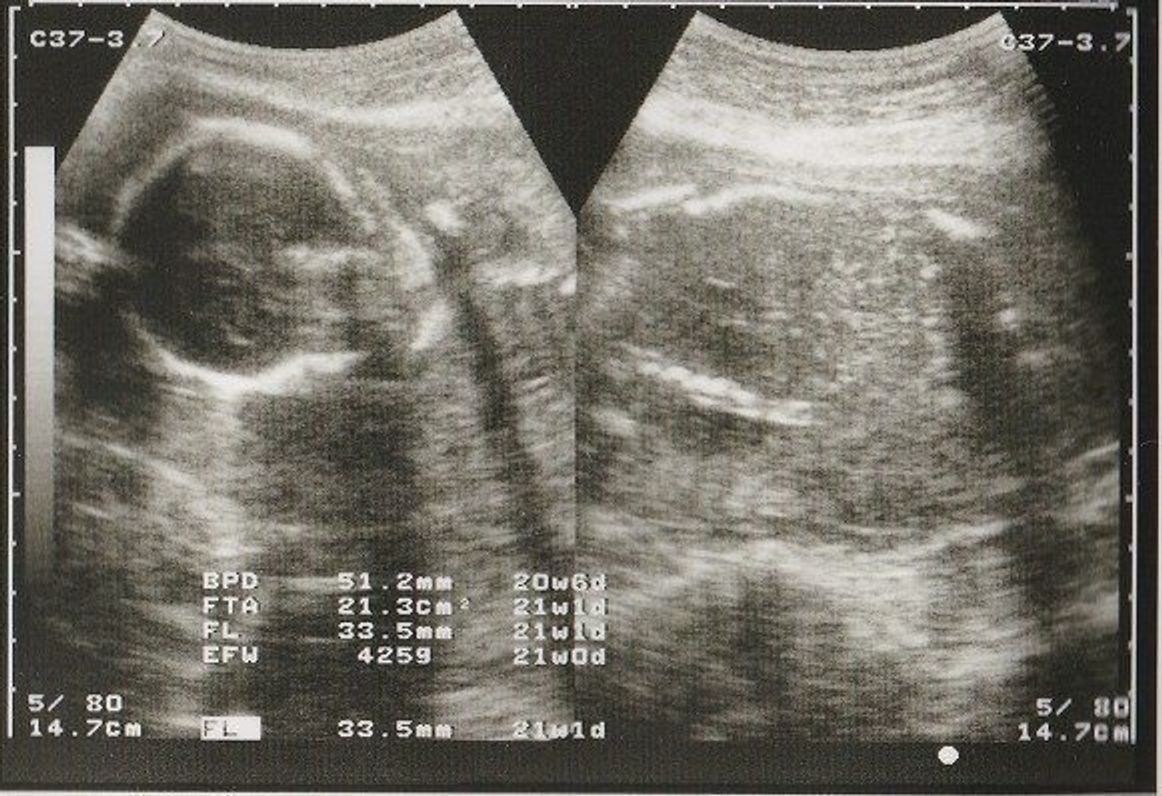

解決済 本日35w2dで検診へ行ってきました。 今まで順調に育ってきてくれてたのですが、今回FL (大腿骨長)が577mmと標準より2wぐらい成長が遅いと指摘されました。 その他の数値は標準だそうです。 念のため来週赤ちゃんのトラブルにも詳しい先生に FL測定が違ってしまうと、当然体重も違ってくるので 余り気にされないで下さい。 医師により、FLが縮んだり、普通よりも足の長い子になっていたり、 いろいろで、そのたびに体重も増えたり減ったり変わらなかったり・・・。

胎児 シェーマ FL 番号 18 19 IUGR 推定体重が妊娠週数に比して小さく,胎児発育曲線上 で-15 SD以下の推定体重をもつ児. symmetrical IUGR(Type 1) 胎児の体重と身長の両方が障害される. asymmetrical IUGR(Type 2) 胎児の頭部の発育はある程度保たれているが まとめ 胎児が大きくなってしまう原因と、出産時に起こるかもしれない問題の可能性についてご紹介しました。 〇遺伝が原因の場合には、母子ともに健康のためほとんど心配はないが、赤ちゃんの大きさが原因の難産は可能性がある。 〇お母さん側の高 妊娠中に気になるのが、お腹の赤ちゃんの成長ですね。 妊婦健診では、胎児の推定体重を計測します。 ここでは胎児の発育の目安と測定方法、測定結果からわかるトラブルについて紹介します。 目次 胎児の発育の目安 まずは胎児成長曲線をチェック

しかし昨日よくよく考えてみると「こんなに差が出るものなのかな? 」と疑問に思いネットでいろいろ調べてみました。 そしたら『足が短い胎児はダウン症の確率が高い』と書いてたサイトを発見しました。 一気に頭の中が暗闇に包まれたような不安と大腿骨長(FL) 350 0 150 100 50 100 150 0 350 300 250 400 250 300 400 8 12 16 24 28 32 36 40 (mm) (週) (週) (mm) 図63 胎児発育曲線(長崎大学) 大横径(BPD),大腿骨長(FL),腹囲(AC)および推定体重をプロットして,経時的な胎児発育を評価します。おなかの赤ちゃん順調に育ってる? "胎児発育曲線"でわかる「大きい・小さい」の意味! (1) 昨年、母子健康手帳が10年ぶりに大リニューアル。 多くのママから寄せられた意見を元に、妊娠中の出来事や気がかりなどを書き込めるメモ欄や、赤ちゃんの

妊娠中の気がかり(体重・食事・病気・体調など) Q 妊娠21週。 胎児の頭が大きく大腿骨が短いと指摘され、とても不安です。 (128) (妊娠週数・月齢)妊娠6か月 (〜23週) 21週目の妊婦健診で、胎児の頭が大きく、大腿骨が短いことを指摘されました 妊娠中の体重増加ペース・子宮底長・腹囲も紹介 妊婦健診前、いつトイレに行こうか毎回悩みました。 (頻尿だと尿検査前にトイレに行くタイミング、難しいですよね。 ) そんな妊婦健診。 尿検査をした後に 体重測定、子宮底長、腹囲などを測定 し